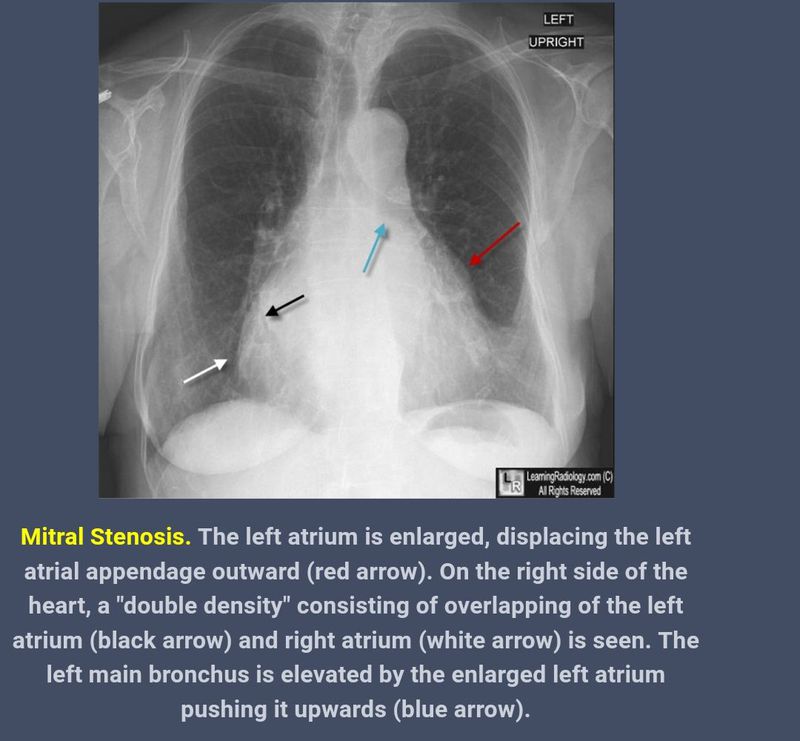

Chest x ray findings of mitral stenosis